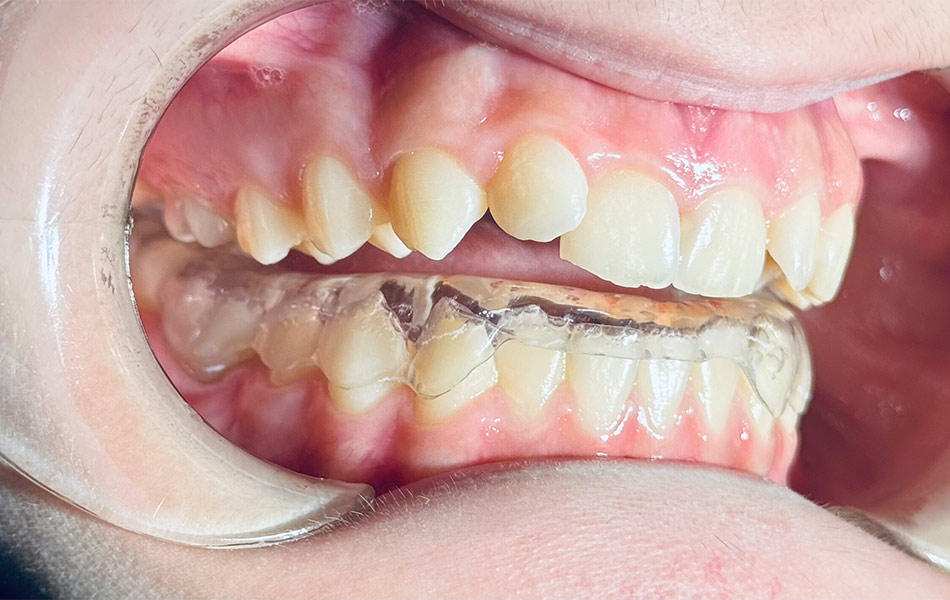

- Ограничение подвижности челюсти — специальные шины или сплинты для расслабления мышц;